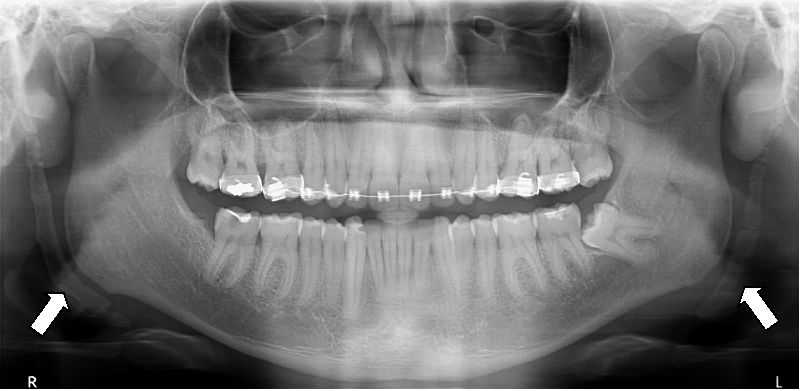

2. What condition can be seen in the following X ray? ( Open arrow)